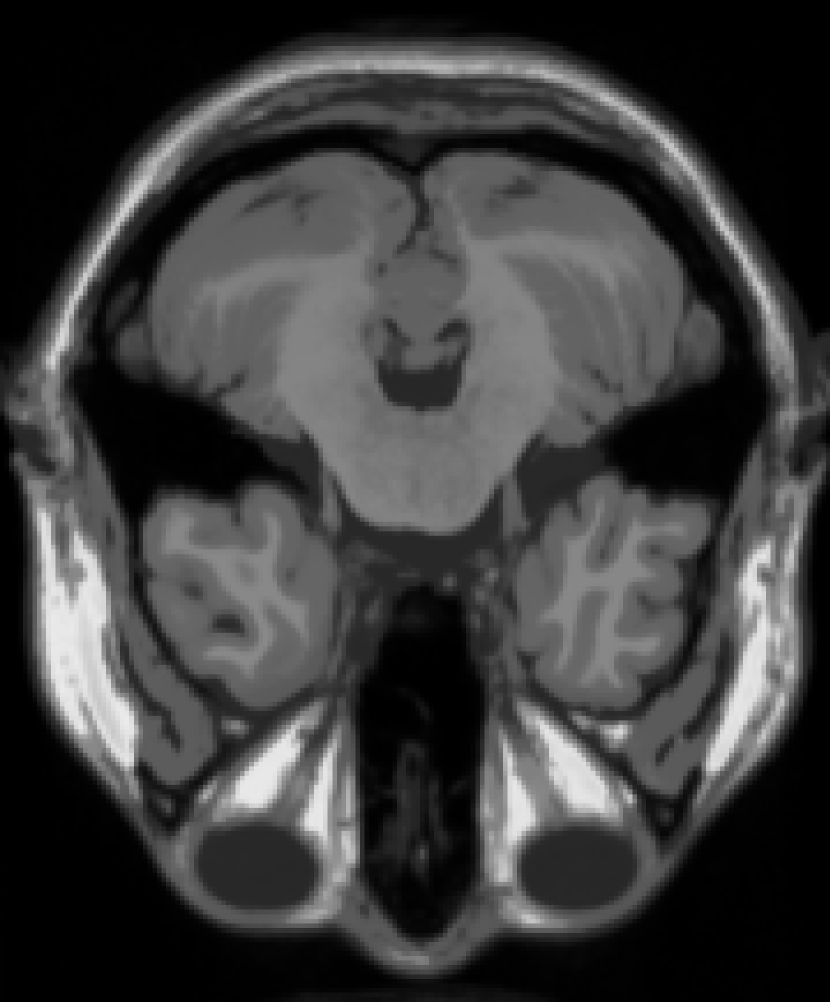

The resolution of the MRI volume dataset333http://graphics.stanford.edu/data/voldata/ is of size with 181 slices and we selected the 38th slice and the 88th slice for the experiment. We consider the case where entries are missing at random by sampling ratio . The GMM noise are set at .

From Figure 12 and Histogram 14, we can see that the effect of FPCA and SVT to restore images is very poor. The effect of VBMFL1 algorithm to restore images is good, but the running time is relatively long. SPG algorithm to restore the image effect and good running time is short. In summary, the SPG algorithm has the best recovery effect.